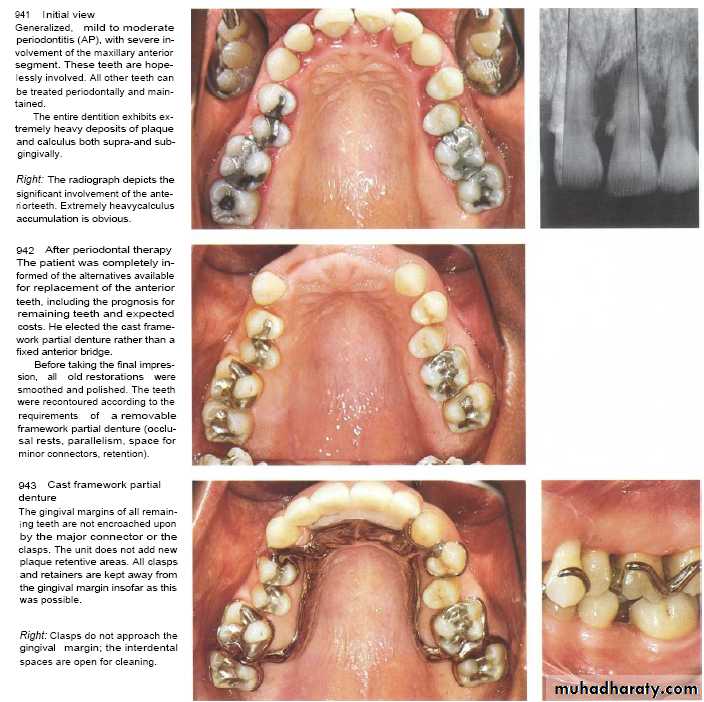

Design of Removable Partial Denture

After the insertion of partial dentures, the mobility of the abutment teeth, gingival inflammation, and periodontal pocket formation increases. These occur due to :-1- retention of plaque.

2- its placement near or above gingival margin.

3- clasp(plaque retentive & exert lateral force ---torque force applied as no occlusal rest).

Partial dentures induce both quantative & qualitative changes in dental plaque(growth of spirochetes).

Chrome cobalt (casted partial dentures) is hygienic one whereas the acrylic is not as it is a temporary prosthesis.

During construction of removable partial dentures ,patient control & occlusal force must be taken in consideration

Free end prosthesis induce damage to anterior teeth by application of leverage torque that result in increase teeth mobility. (dental implant is solution)Acrylic partial dentures should be wear for temporary period with its margin placed away at least 4mm from gingival margin.

Clasp should be constructed with occlusal rest & on canine tooth must construct a U-shape clasp.

In casted partial dentures---the presence of occlusal rest & margin away from gingiva are kept the adjacent periodontium healthy but also it may also increase gingival inflammation & periodontal pocket formation due to plaque accumulation especialy if its worn day & night .